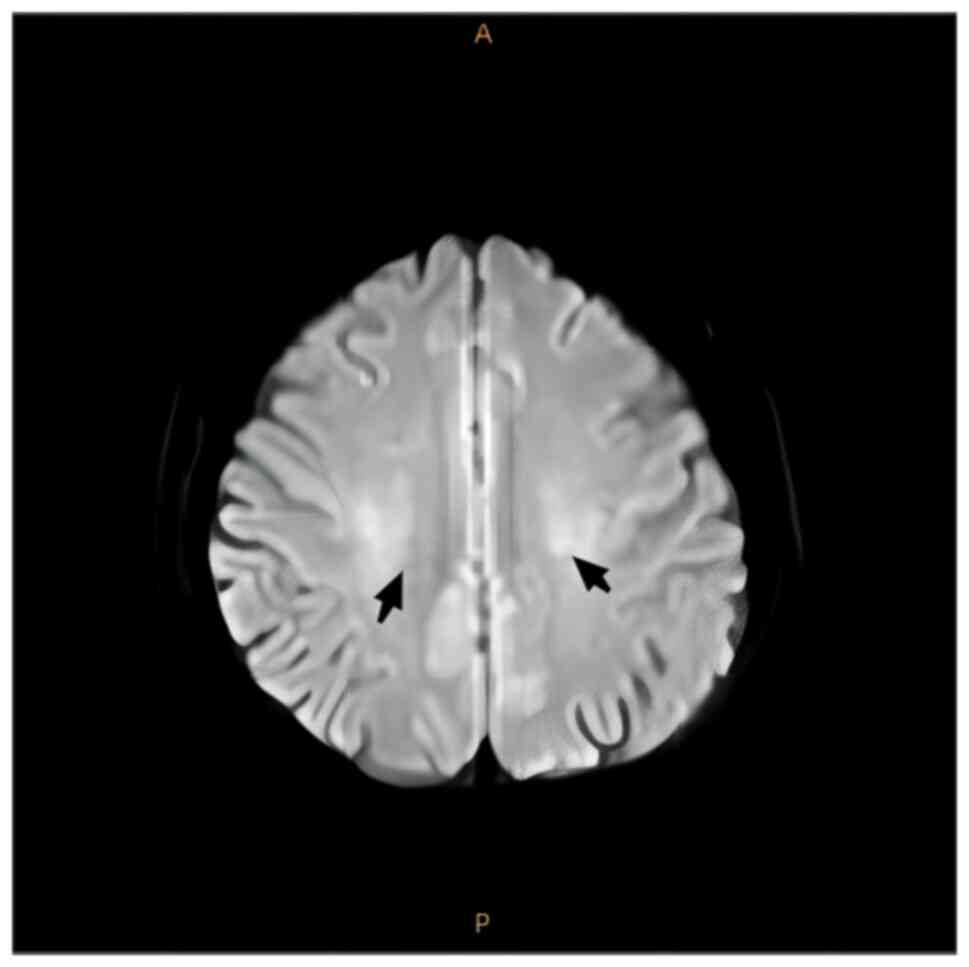

4). MRI of the brain demonstrated

spot-like and short-stripe abnormal signals that were distributed

symmetrically in the centrum semiovale, with equal or a slightly

low signal intensity on T1W1 and a slightly high signal intensity

on T2W1 (Fig. 5) and

hyperintensity on fluid-attenuated inversion recovery (FLAIR;

Fig. 6). Diffusion-weighted

imaging revealed low signal intensity (Fig. 7) and the long axis of the lesion

was perpendicular to the lateral ventricles. The patient was

finally diagnosed with SCD.

After 6 months of follow-up treatment, cranial MRI

images demonstrated that the symmetrical spot-like and short-stripe

abnormal signals in the centrum semiovale were reduced compared to

previous scans (Fig. 8). The Hcy

and serum vitamin B12 levels of the patient were also within the

normal range.

weakness, sensory ataxia and paraesthesia (11). In the present study, the patient's

lesions were mainly in the bilateral centrum semiovale as there was

a high signal in this region on T2 MRI and FLAIR. In the present

study, the lesions were symmetrical and perpendicular to the long

axis of the bilateral lateral ventricles, which is a characteristic

manifestation of SCD. These lesions are either directly or

indirectly related to the vitamin B12 deficiency observed in the

patient.